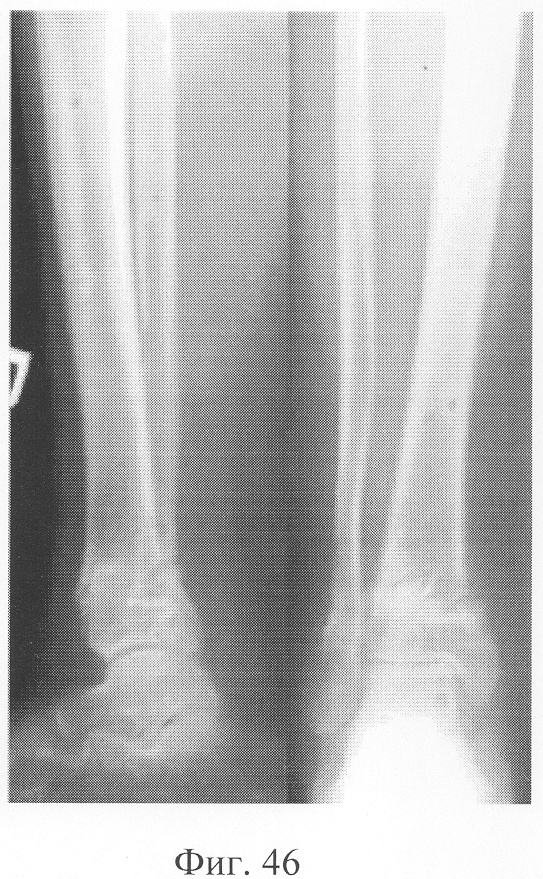

Больной Р., 46 лет, поступил для планового оперативного лечения с диагнозом «ложный сустав правой большеберцовой кости с варусно-антекурвационной деформацией» (фиг.34-37 клинико-рентгенологические данные до операции). Предшествующее лечение перелома проводилось консервативным способом, можно отметить несостоятельность и недостаточную продолжительность иммобилизации, что является у данного пациента основным фактором в формировании ложного сустава. Из сопутствующей патологии необходимо отметить гипертоническую болезнь II ст., ИБС, атеросклеротический кардиосклероз, НК II А ст. Во время операции произведена экономная резекция фрагментов, устранение деформации в аппарате внешней фиксации, костная пластика деминерализованным костным трансплантатом, заселенным аутологичными мезенхимальными стволовыми клетками, по предложенной методике (при этом костный паз был выполнен по внутренней поверхности в области диастаза между костными фрагментами). В послеоперационном периоде дренажи удалены на 2-е сутки, швы сняты на 21 сутки в связи с развитием краевого некроза в области послеоперационной раны. Ходьба при помощи костылей с 7-х суток послеоперационного периода, дозированная нагрузка на конечность с третьего месяца после операции с учетом локализации повреждения в дистальной части большеберцовой кости (фиг.38-42 – клинические и рентгенологические данные в процессе лечения). Из осложнений необходимо отметить воспаление в области чрескостных элементов в конце периода фиксации, что купировано после снятия аппарата. Демонтаж аппарата внешней фиксации через 5,5 месяцев при клинико-рентгенологической картине сращения.

При рентгенологическом и томографическом контроле в динамике отмечалось отчетливое нарастание плотности костной ткани в трансплантатах без предварительной резорбции (фиг.43 – динамика рентгенологической и томографической картины). Таким образом, развившиеся воспалительные процессы были своевременно купированы и не сказались на результате лечения (фиг.44-46 – результат лечения).